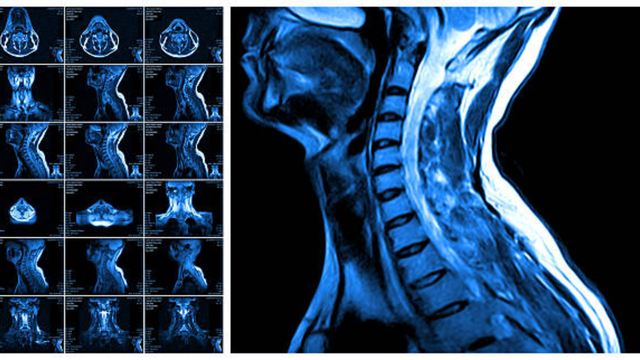

Tổng hợp các bài viết sức khỏe chủ đề chụp ct